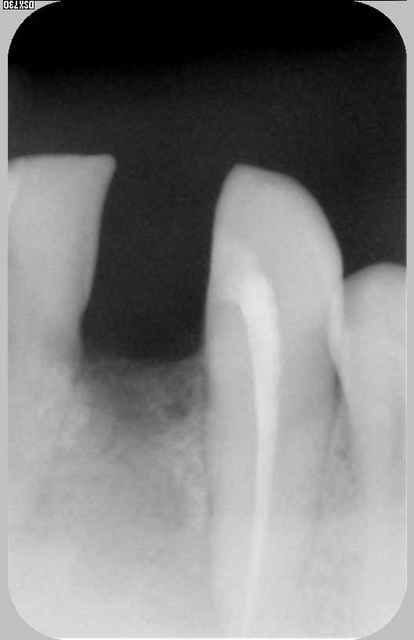

Euh je ne veux pas être négatif mais je dirai plutôt une cratérisation établie; ton os arrivait à la spire distal n°10 (à l'origine) maintenant il est bien en dessous :-(

pourquoi penses tu que je parle de "pseudo" réossification et de cone morse : aucune étanchéité autour du bricolage qui présente encore moins d'étanchéité qu'un connectique à plat

les contraintes que montraient Haig sont bien toujours présentes même si soulagées par le fait que l'on ait "acastillé" l'autre coté .

il s'agit d'un sauvetage la corticale en linguale est toujours présente mais poche en vestibulaire car l'axe de cet implant n'est pas non plus idéal en vestibulo lingual comme mésio distal ya pas de raison:-))